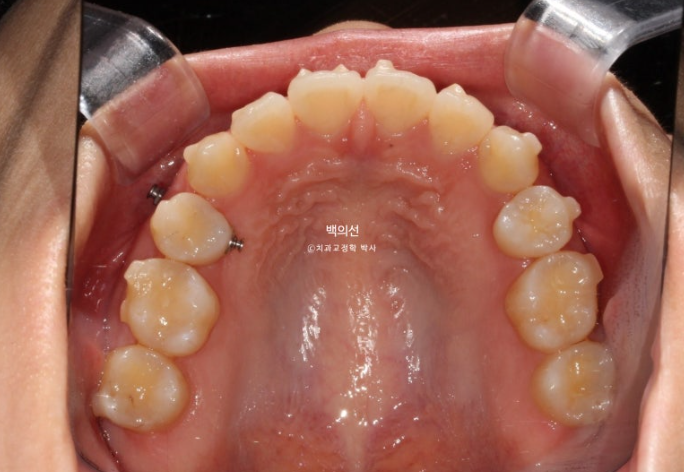

그리고 치료 시작 10개월차, 교합면 사진을 보면 마치 발치공간이 다 닫힌것 처럼 보입니다.

남아있던 발치공간은 깔끔히 마무리 되었습니다.

발치공간은 어금니 쓰러짐 없이 잘 닫혔고

발치곡안이 미세하게 남아 두번째 추가장치 제작에 들어갔습니다.